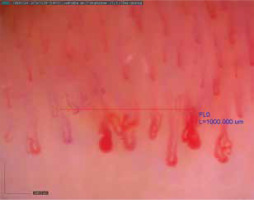

Scleroderma-like microangiopathy is found in about 40–50% of cases of scleroderma-spectrum disorders [10]. It is observed in about 20–40% of patients with idiopathic inflammatory myopathies, more often in DM than in PM, especially when accompanied by the Raynaud’s phenomenon. Manfredi et al. have suggested that capillaroscopic changes typical of microangiopathy are associated only with DM and not with MCTD [11]. Characteristic vascular abnormalities in DM are neoangiogenesis (bushy, dendriform vessels), moderate disorganization of the vascular system with a relatively low number of avascular areas. Moreover, bushy and dilated vessels predominate (Figure 1) [3]. Considering significant differences in capillaroscopic images of SSc patients compared to DM patients, Mugi et al. have implied that in DM the term “microangiopathy in the course of DM” should be used instead of “scleroderma-like microangiopathy” [12]. Furthermore, Sebastiani et al. have demonstrated capillaroscopic abnormalities in 62% of patients with antisynthetase syndrome; the pattern of scleroderma-like microangiopathy has been found to correlate with the presence of anti-Jo1 antibodies, yet not with the Raynaud’s phenomenon [13]. On the other hand, more than 40% of patients with idiopathic inflammatory myopathies have normal capillaroscopic images, and some have nonspecific changes [10].

According to the literature data on MCTD, the scleroderma-like capillaroscopic changes are found in about 50% of MCTD patients; in 20% the changes are non-specific while in 30% the images are normal. The early pattern of scleroderma-like microangiopathy predominates (Figure 2) [10]. In their retrospective assessment of capillaroscopic images in patients with MCTD, UCTD and primary Raynaud’s phenomenon, Pizzorni et al. have demonstrated that the incidence of scleroderma-like microangiopathic capillaroscopic changes was statistically significantly higher in the group of patients with MCTD, as compared to UCTD [5]. Moreover, the presence of neoangiogenesis, giant capillaries and capillary reduction was more pronounced in MCTD than in UCTD. The authors have concluded that the capillaroscopic abnormalities in UCTD resemble the images observed in the primary Raynaud’s phenomenon (nonspecific changes), as opposed to MCTD in which scleroderma-like microangiopathic changes prevail.

Figure 2

Capillaroscopic changes in mixed connective tissue disease (scleroderma-like pattern microangiopathy)